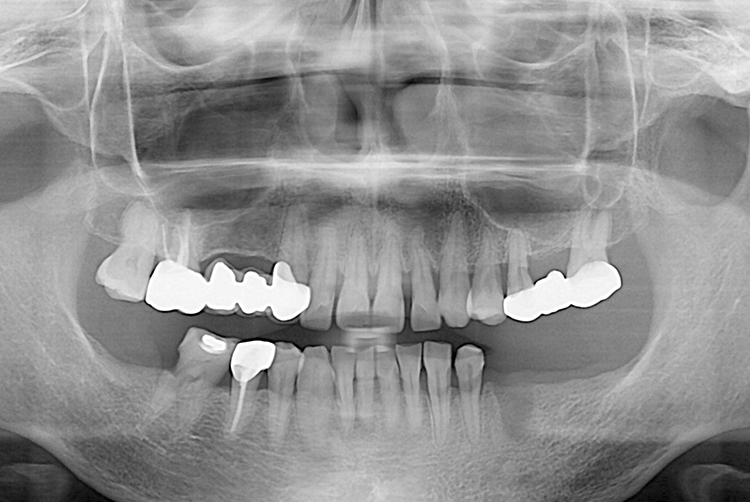

PX20220329_140940_0000_0000F9E9.jpg

치료후 : 2022-03-29

세종치과는 많은 환자와 다양한 케이스를 바탕으로 항상 편안한 임플란트 수술을 제공하고자 노력하고,

오래동안 튼튼히 쓸 수 있는 임플란트 수술을 가장 큰 목표로 삼고 있습니다